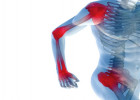

Сегодня разберем, как проходит артроскопическая пластика связок, кому она нужна и как восстановиться без лишних ошибок. Сразу важно сказать: в СМ-Клиника https://centr-hirurgii.ru/surgery/operativnaya-travmatologiya-ortopediya/artroskopicheskaya-plastika-svyazok/ такие операции выполняют по современным протоколам, с коротким стационаром и четким планом реабилитации.